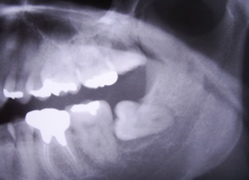

平成6年の時の写真です。

右下に親知らずがありますが、症状もなく放置しております。

手前の銀歯の適合も良く有りませんが、これも症状がなく放置しております。

それから17年が経過しました。

親知らずはまるで手品のように傾いています。ほぼ逆さまに近い状態です。

レントゲンで黒くなっている透過像を見て「悪性腫瘍では?」という最悪の事態も考えました。

紹介先の日鋼記念病院で入院。抜歯を含む手術を行いました。

悪性腫瘍でなくホッとしました。

平成6年に説得して抜いていれば、、、悔やまれます。